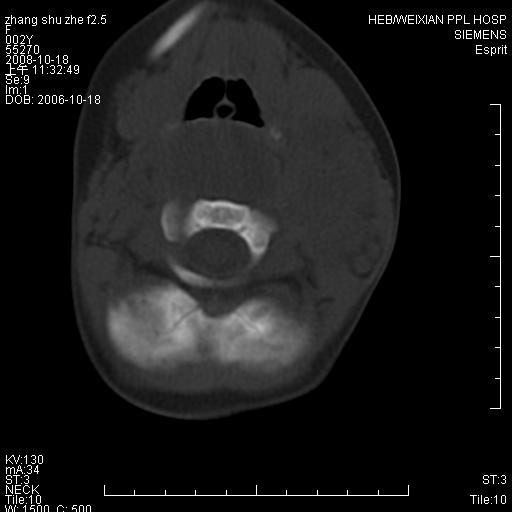

以下是引用dyqct在2009-2-10 21:04:00的发言:[br]年龄?性别?有发烧吗?[br]鼻咽部、口咽部、喉咽部及颈椎前间隙广泛肿厚,明显占位效应并致相应组织变形。ct值22-28hu。[br]考虑:1、颈前脓肿可能性大;[br] 2、建议增强或治疗后复查。

以下是引用jiangjing在2009-2-11 11:37:00的发言:[br]急性病程,鼻咽部、口咽部、喉咽部及颈椎前间隙广泛肿厚,明显占位效应并致相应组织变形.考虑颈部感染性病变(脓肿?);建议行进一步检查。